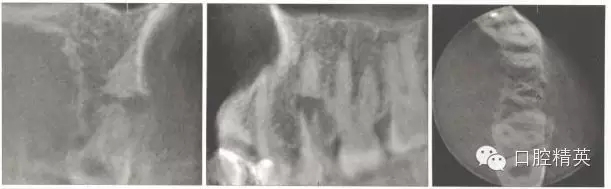

錐形束CT示:斷端處根中上部和下部完全分開,斷端根尖部未見根管影像。斷端呈喇叭口狀,斷端的近遠(yuǎn)中側(cè)均有骨質(zhì)破壞(圖3)。

圖3 初診錐形束CT影像